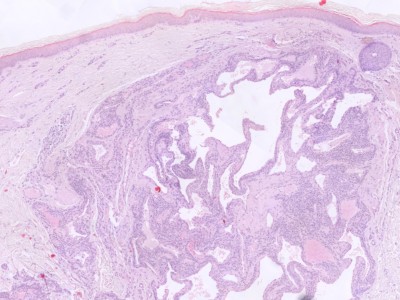

Solitaire laesies: omschreven noduli omgeven door bindweefsel, opgebouwd uit vaatruimten omgeven door clusters ronde of polygonale cellen met plompe kernen en eosinofiel cytoplasma (glomuscellen). Multipele glomustumoren zijn minder goed omschreven en lijken meer op hemangiomen, met multipele, grote, irregulaire verwijde vaatruimten. Focaal in de vaatwanden zijn aggregaten van glomuscellen aanwezig.

Histologie glomangioom Histologie glomangioom

ingescande coupe (zoom) ingescande coupe (zoom)